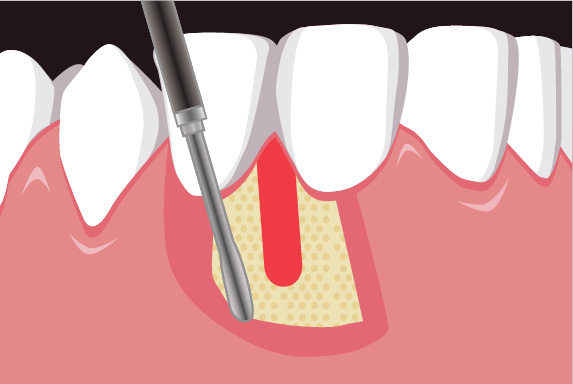

理事長の菅は日々新たな歯科治療の技術や知識を学び、それを臨床の現場に反映しています。再生療法の世界的な権威のDr. Cortellini 歯周組織再生治療のセミナーを受講。

専門医資格を持つ医師が歯周組織再生治療を手がけるので、安心して治療を受けていただけます。